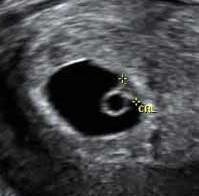

5 седмица